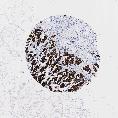

UROTHELIAL CANCER - Protein expressioni

A mouse-over function shows sample information and annotation data. Click on an image to view it in a full screen mode. Samples can be filtered based on level of antibody staining by selecting one or several of the following categories: high, medium, low and not detected. The assay and annotation is described here.

Note that samples used for immunohistochemistry by the Human Protein Atlas do not correspond to samples in the TCGA dataset.

Antibody stainingi

Antibody staining in the annotated cell types in the current human tissue is reported as not detected, low, medium, or high, based on conventional immunohistochemistry profiling in selected tissues. This score is based on the combination of the staining intensity and fraction of stained cells.

Each image is clickable and will lead to virtual microscopy that enables deeper exploration of all samples and also displays staining intensity scores, fraction scores and subcellular localization as well as patient and tissue information for each sample.

Antibody HPA002465

Antibody CAB000031

Urothelial carcinoma, High grade

Urothelial carcinoma, Low grade

Adenocarcinoma, NOS